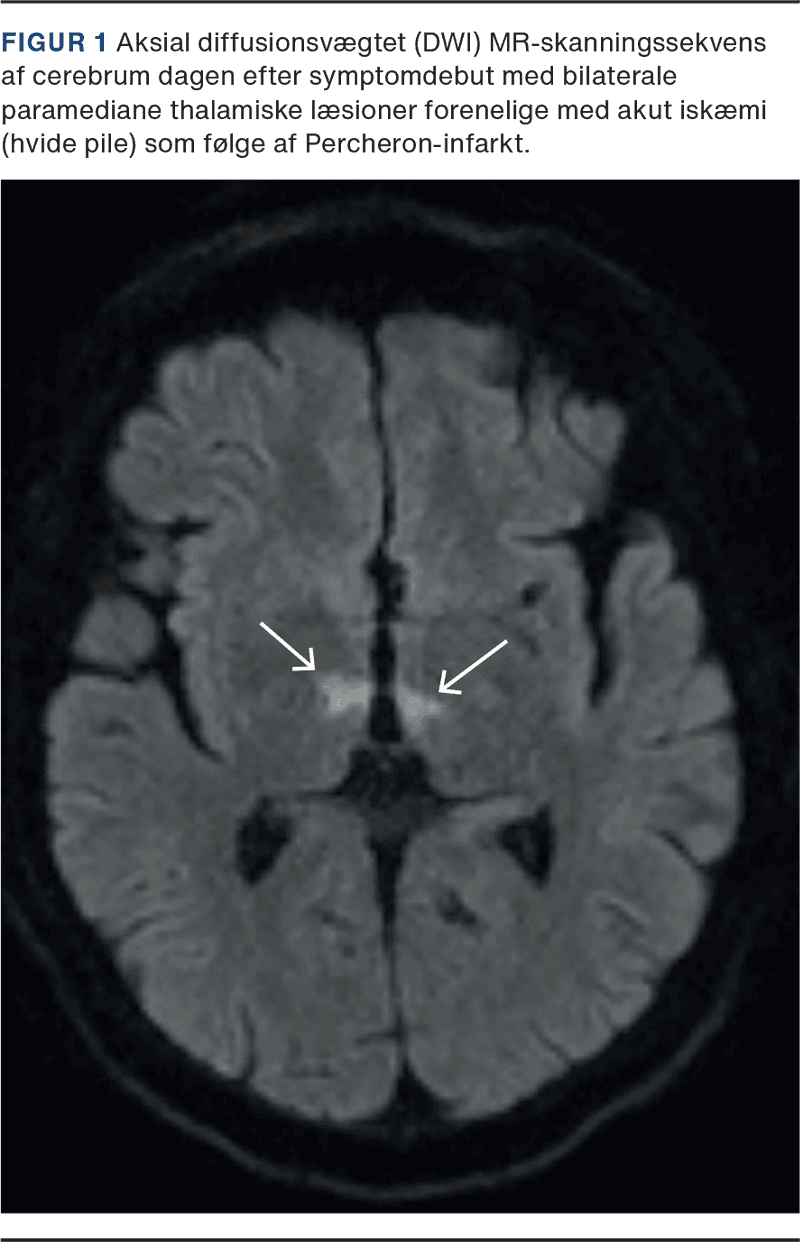

Dagen efter blev han vurderet i trombolyseregi, hvor trombolysevagten fandt dysartri, vertikal blikparese og bilateralt ekstensivt plantarrespons; National Institute of Health Stroke Scale (NIHSS = 7). MR-skanning af cerebrum viste fluid-attenuated inversion-recovery (FLAIR)-positive infarkter i begge thalami og mesencefalon forenelige med et Percheron-infarkt (Figur 1). CT-angiografi var uden storkarsokklusion eller dissektion. Han blev udskrevet til en døgngenoptræningsplads en uge senere og var på dette tidspunkt ikke længere bevidsthedspåvirket men havde fortsat let talebesvær og nedsat overblik.